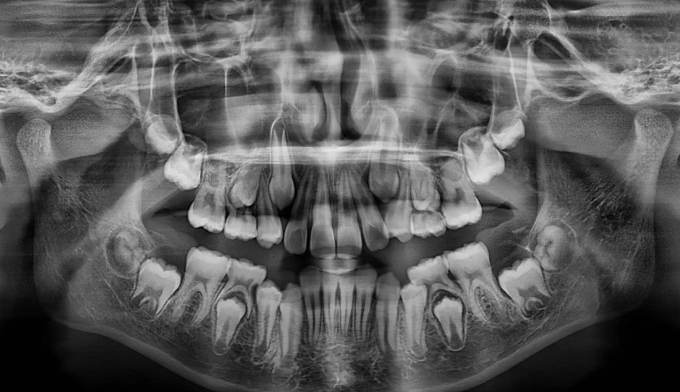

송곳니가 나올 공간이 전혀 없어 보입니다.(화살표로 표시한 부분이 송곳니가 나와야 할 공간입니다)

안모를 고려하여 앞니가 앞으로 뻗치지 않게 주의하면서 어금니만 후방이동시켜 송곳니가 맹출할 공간을 만듭니다.

총 교정기간은 13개월이 소요되었습니다.